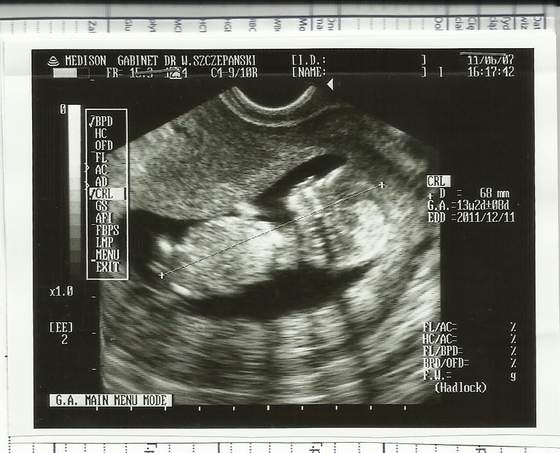

Ja też nareszcie się doczekałamBabel popisał się nawet saltem

takie jakieś "surowe" to USG, czułam się bardziej jakbym była w urzędzie niż u lekarza po całej tej wizycie. Jedyne co usłyszałam od pani monitorującej to : tutaj jest serce i dzidzia wygląda zdrowa. Z karty przeczytałam, że ma prawie 53mm, przyzierność 1,5 mm, więc chyba w porządku (ale lekarska opinia dopiero po badaniu krwi), glowa wygląda normalnie(to raczej nie po mamusi

). Nawet nie powiedziała wieku (ten ze zdjęcia jest kalendarzowy), może będzie jak przyjdą wynki. Tak bardzo się cieszę.